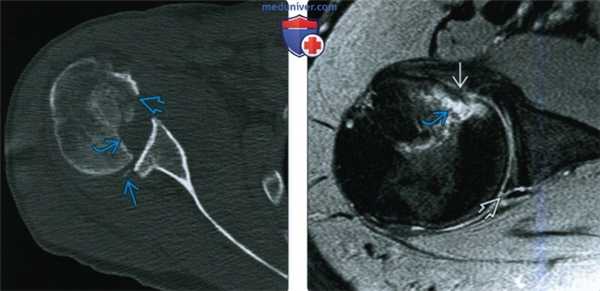

(Слева) На осевой КТ после вправления вывиха определяется обратный перелом Банкарта, обратный вдавленный перелом Хилла-Сакса и перелом малой бугристости. При заднем вывихе переломы малого бугорка встречаются часто.

(Справа) На осевой MPT PDВИ FS после вправления заднего вывиха визуализируется небольшой обратный вдавленный перелом Хилла-Сакса с сопутствующим ушибом кости. Кроме того, имеется разрыв задней губы, обратное повреждение Банкарта.

3. КТ при заднем вывихе плеча:

• Перед открытым вправлением: дооперационное планирование:

о Величина обратного повреждения Хилла-Сакса

о Наличие обратного перелома Банкарта

• После вправления: оценивают переломы, которые плохо видны на рентгенограмме:

о Привычные вывихи могут привести к дефекту или дефициту заднего края суставной впадины